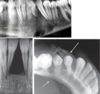

The wall of which cyst?

Periapical Cyst

Open clear areas = Cholesterol clefts where fat

used to be. Multinucleated cells (purple dots)

trying to break down cholesterol

What is this and what is it associated with?

keratin pearl – can be associated w/SCC